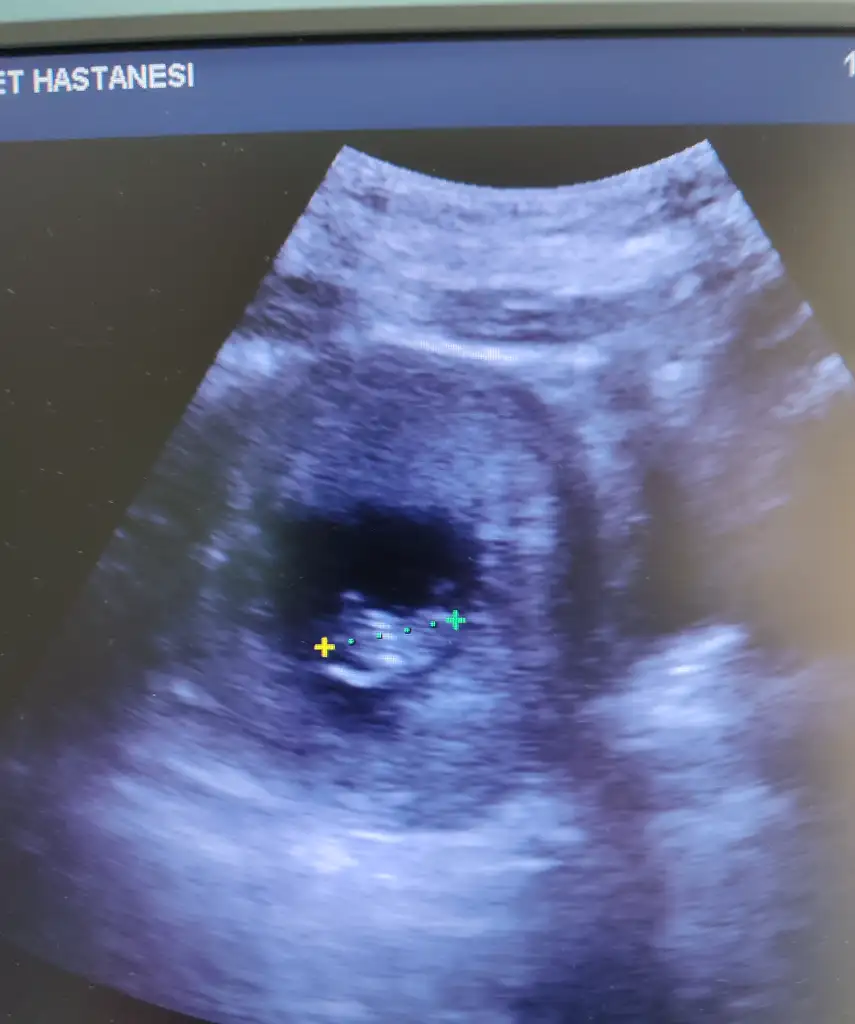

Büyümüş fasulye 9+1 ile uyumlu çıktı yumurtlama ya göre tam gününe uygun cok şükür bir sıkıntımız yok 🥰 sizce cinsiyet neye benziyor fikriniz varmı 🤭